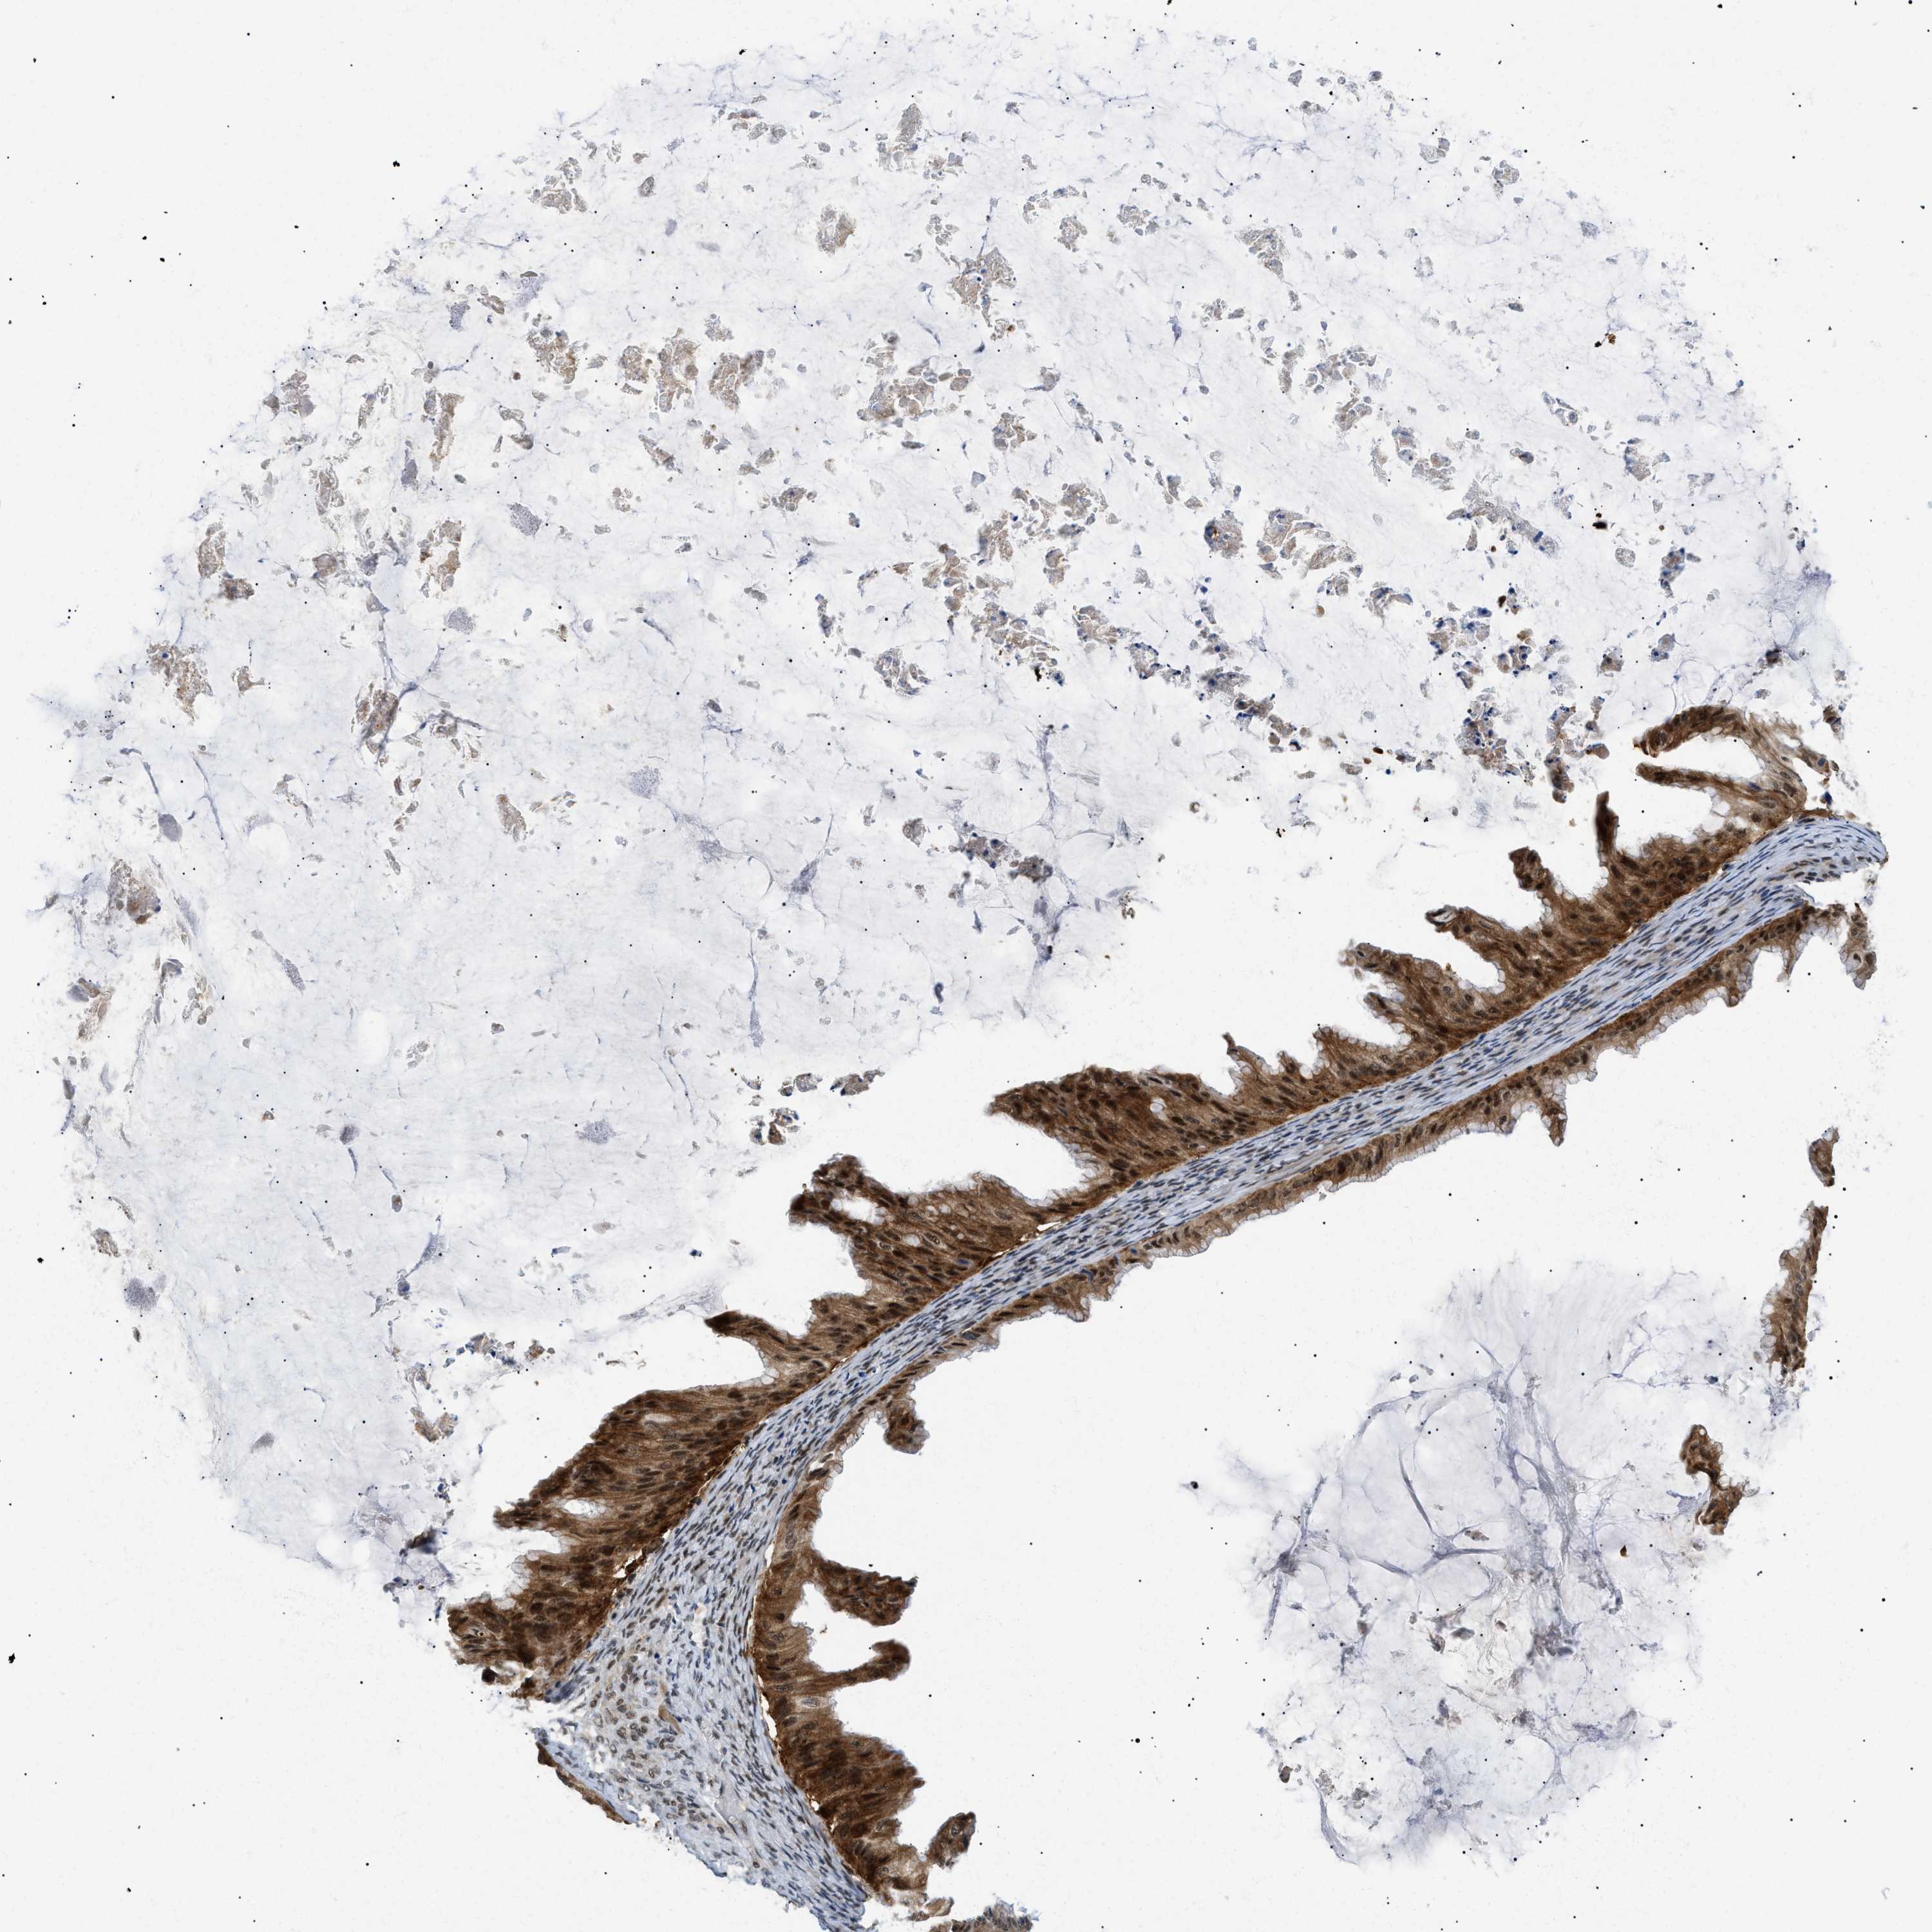

OVARIAN CANCER - Protein expressioni

A mouse-over function shows sample information and annotation data. Click on an image to view it in a full screen mode. Samples can be filtered based on level of antibody staining by selecting one or several of the following categories: high, medium, low and not detected. The assay and annotation is described here.

Note that samples used for immunohistochemistry by the Human Protein Atlas do not correspond to samples in the TCGA dataset.

Antibody stainingi

Antibody staining in the annotated cell types in the current human tissue is reported as not detected, low, medium, or high, based on conventional immunohistochemistry profiling in selected tissues. This score is based on the combination of the staining intensity and fraction of stained cells.

Each image is clickable and will lead to virtual microscopy that enables deeper exploration of all samples and also displays staining intensity scores, fraction scores and subcellular localization as well as patient and tissue information for each sample.

Antibody HPA019824

Antibody CAB015201

Staining

High

Medium

Low

Not detected

Intensity

Strong

Moderate

Weak

Negative

Quantity

>75%

75%-25%

<25%

None

Location

Nuclear

Cytoplasmic/membranous

Cytoplasmic/membranous,nuclear

Cystadenocarcinoma, serous, NOS

Carcinoma, endometroid

Cystadenocarcinoma, mucinous, NOS

Carcinoma, NOS